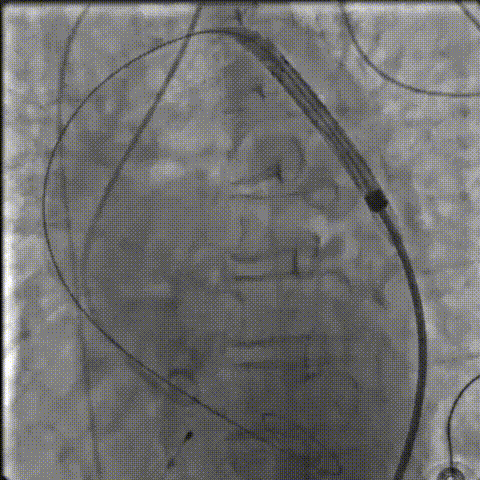

过弓、跨瓣

零位定位

工作位造影

零位定位逐步释放至工作位,多角度评估位置良好

缓慢脱钩至完全释放,最终植入位置理想

AV26瓣膜工作位造影

缓慢脱钩